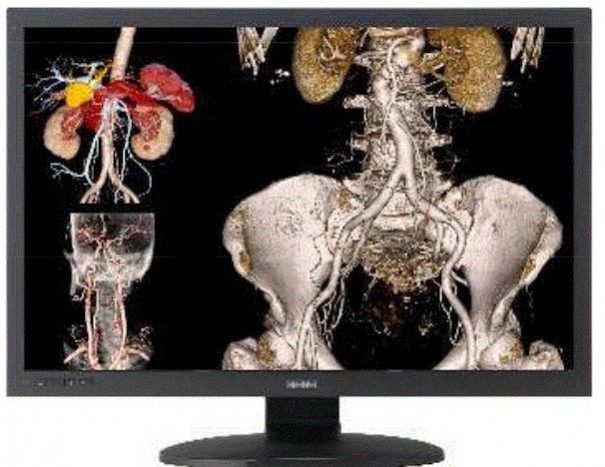

Tras la adquisición del negocio de displays médicos de Totoku, JVCKenwood sigue apostando por el desarrollo de su línea de negocio centrada en el entorno de la salud. La última actuación estratégica ha sido la alianza firmada con Sysmex para desarrollar conjuntamente instrumentos de diagnóstico para la medición de exosomas, elementos que pueden ser utilizados en las pruebas para detectar ciertas enfermedades.

La compañía está haciendo esfuerzos para hacer crecer su área de negocio de salud, que incluye en la actualidad diversos sistemas para imágenes de diagnóstico y apoyo quirúrgico. Como un aspecto importante en esa área de trabajo, ha desarrollado tecnologías de disco óptico para detectar y contar exosomas utilizando nanoesferas, una técnica basada en las soluciones ópticas adoptadas en sus unidades Blu-ray y DVD.

En este desarrollo conjunto, JVCKenwood hará uso de las tecnologías de disco óptico utilizando nanoesferas para el desarrollo de instrumentos de medición capaces de capturar y contar los exosomas existentes en la sangre. Sysmex también desarrollará instrumentos para la medición de las sustancias contenidas en ellos, usando tecnologías propias de medición para el análisis de genes y de proteínas.